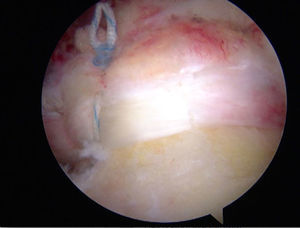

En la técnica de fila sencilla o una sola fila se colocan anclajes de 5,0 o 5,5 mm (titanio biodegradable o peek) en el margen lateral de la tuberosidad mayor, se pasan los puntos a través del tendón aproximadamente a 15 mm en sentido medial al borde de la rotura. Se utiliza el número de anclajes de acuerdo con el tamaño de la rotura. También se debe tener en cuenta con cuántas suturas está cargado el anclaje. En la mayoría de diseños tiene dos suturas reforzadas. Para las roturas en forma creciente se puede realizar la reparación con puntos sencillos, pero, cuando son lesiones de mayor extensión o en forma en L, se recomienda combinar puntos de borde a borde y fijación con anclajes (figs. 14–16).